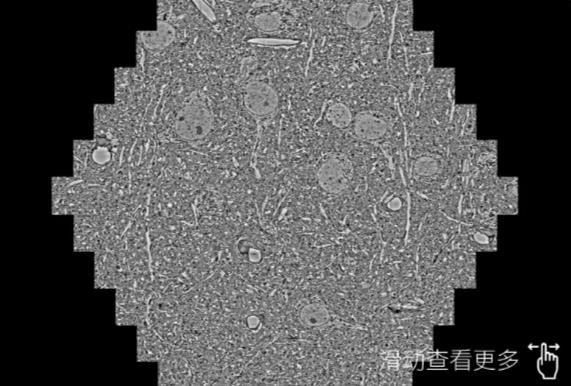

鼠脑切片。左图使用北碚蔡司北碚扫描电镜MultiSEM706对165μmx143pm面积区域成像,耗时仅需1.5秒。右图为鼠脑切片中30μm区域放大效果。样品由芝加哥大学B.Kasthuri提供。

使用蔡司高速北碚扫描电镜MultiSEM对1mm²人脑皮层组织进行高分辨成像,并对其中的各种细胞结构进行三维重构分析。左图展示了2x3mm²组织平面中锥体神经元的三维重构效果。右图显示了局部体积神经元三维重构。图像由哈佛大学chtman实验室提供,渲染图由D. Berger 制作。